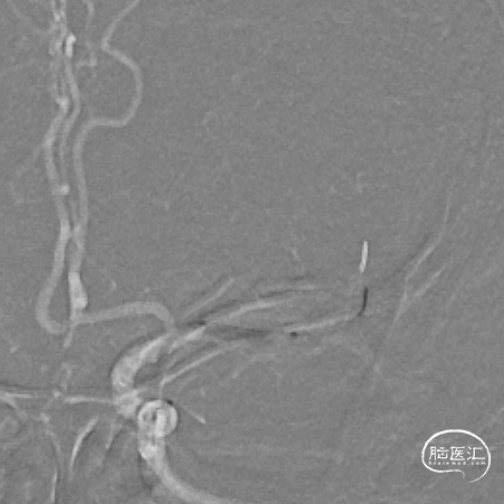

最后路径手推造影,造影确认脑血流完全恢复,mTICI 3级。

术后复查CTA:提示左侧大脑中动脉通畅,支架在位。